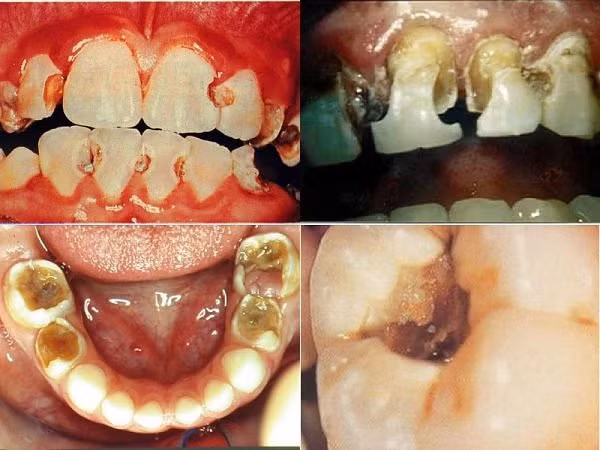

Người tiêu thụ đường tự do trên 10% tổng số nhu cầu năng lượng hay ăn các món có đường tự do trên bốn lần trong ngày sẽ tăng nguy cơ bị sâu răng. Đường tự do gồm tất cả đường đơn, đường đôi, ví dụ glucose, sucrose (đường mía), fructose (đường trái cây), dextrose...

| Sâu răng (Ảnh minh họa/ Nguồn: Internet) |

Những loại đường này có thể xuất phát từ tự nhiên như đường mía, đường trái cây, cũng có thể là đường công nghiệp thêm vào bánh, kẹo, kem. Các loại thực phẩm dễ gây sâu răng bao gồm kẹo, nước ngọt, bánh ngọt, bánh snack, bánh bông lan, trái cây ngọt, chè các loại, kem... Tinh bột trong cơm, khoai, bánh mì không tăng nguy cơ sâu răng.

Bên cạnh sâu răng, mòn men răng cũng liên quan đến dinh dưỡng. Các nhà khoa học thấy rằng thực phẩm mang tính acid, ví dụ như trong nước ngọt và các loại nước trái cây, có thể làm giảm độ pH của vùng men răng làm mòn dần lớp men răng (men răng chịu được độ pH tối ưu ở mức 5.5). Mòn men răng kéo dài làm giảm kích thước răng và nặng là phá hủy răng.